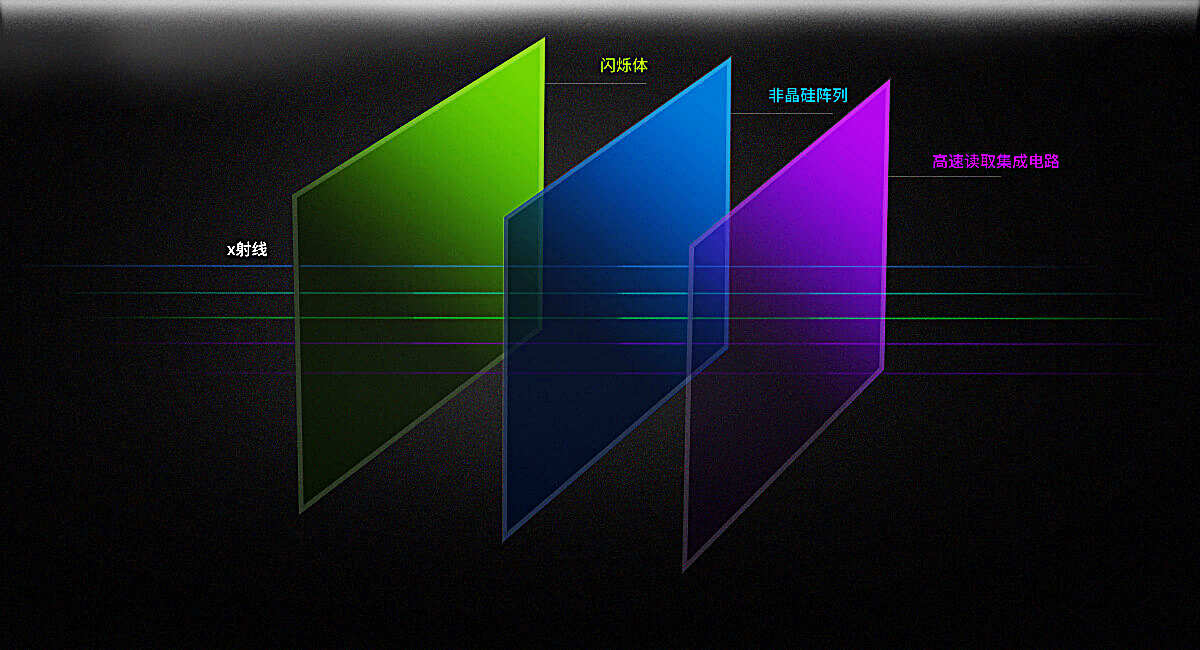

高清动态平板探测器

搭载自主研发超清大视野动态平板探测器,600微米碘化铯大幅提升X线转化效率,独特的非晶硅阵列与高速读取集成电路紧密协作,轻松实现多帧率透视与高清点片。

17x17英寸

900万

0.8S

DFP同步曝光

线性探测平面

图像无畸变、无失真